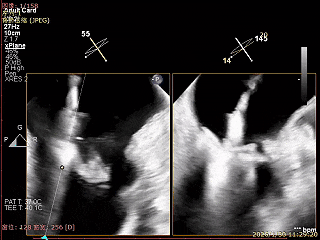

夹子关紧后,前后叶受限明显

夹子内侧反流消失

夹子外侧残余脱垂与反流

3D Enface下组织桥稳定残余外侧前叶脱垂

3D Enface上彩可见夹子内侧无反流,残余外侧反流

送入第2枚XTR在左房调整轨迹及Orientation

进入瓣下重新确认Orientation及位置

捕捞瓣叶,确定瓣叶瓣尖稳定插入夹臂后,Gripper Down

关紧后,前后叶受限明显

3D Enface下组织桥稳定无反流

夹子释放后,反流基本消失

LVOT切面可见主瓣二尖瓣术后反流基本消失